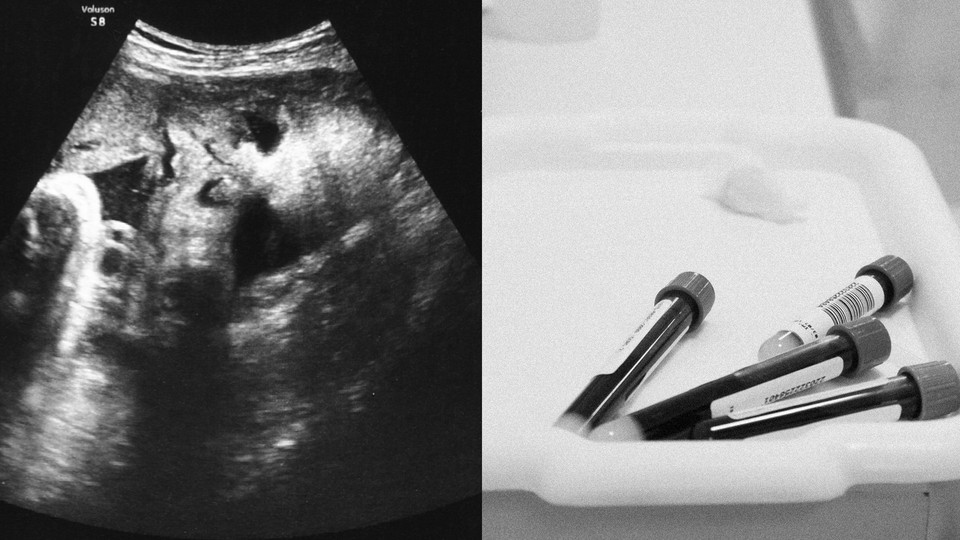

For expectant parents, pregnancy can be a time filled with joyful anticipation: hearing the beating of a tiny heart, watching the fetus wiggling through the black-and-white blur of an ultrasound, feeling the jostling of a little being in the belly as it swells.

That may soon change. Scientists are learning that free-floating bits of genetic material found in a pregnant person’s blood may offer a way to detect complications such as preeclampsia and preterm birth—although some experts caution that it’s too early to determine how useful these tests will be in the clinic. In the meantime, the tests are providing researchers with a new way to unravel the underlying biology of these inscrutable ailments.

All of us carry bits of our own genetic material—both DNA and its more evanescent cousin, RNA—around in our bloodstreams. During pregnancy, these free-floating fragments, known as cell-free DNA and RNA, are also released from the developing fetus into the mother’s blood, primarily via the placenta. For more than a decade, clinicians have used cell-free DNA from blood to screen the fetus for genetic abnormalities.